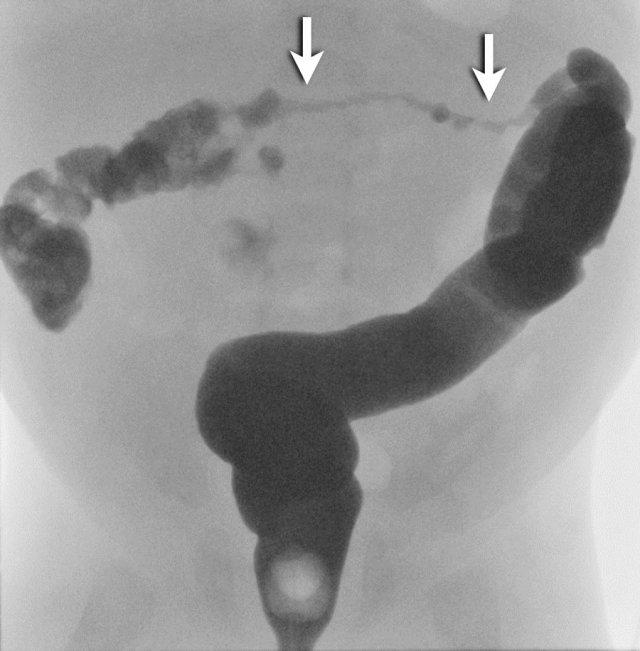

Đây là hai trường hợp tắc ruột phân su.

Có hình ảnh đại tràng nhỏ và nhiều viên phân su ở đoạn ruột non xa (mũi tên).

Hội chứng nút phân su: trực tràng bình thường và đại tràng trái có khẩu kính nhỏ. Do trẻ có trực tràng chức năng bình thường nên tiếp tục tống xuất thuốc cản quang và phải sử dụng ống thông có bóng chèn.